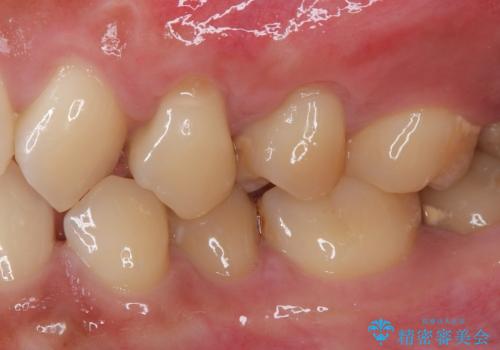

- 食いしばりと強いブラッシングにより、上顎小臼歯2本に知覚過敏を感じるようになったとのことで来院された患者様です。

歯肉退縮により歯根部が露出し、冷たい飲み物に痛みを感じる状態でした。

根面被覆を目的として歯肉移植術を行うこととしました。

歯肉が薄い状態であったため、歯肉退縮が起こりやすいと判断された患者様でした。

根面被覆を達成するとともに、歯肉の厚みを増すことで、今後歯肉退縮を起こしにくくするよう配慮した処置としました。